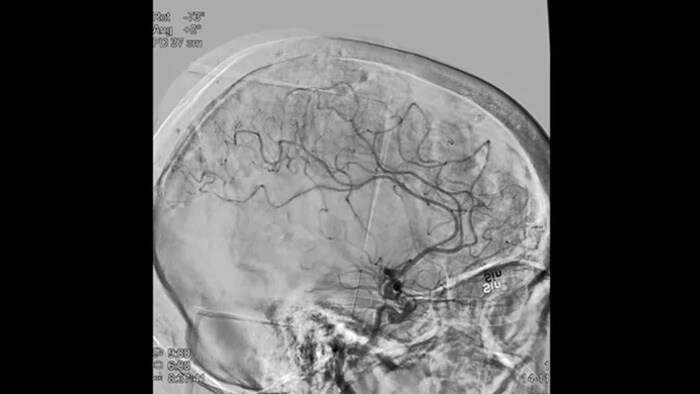

Scherpe beelden met DSA met ClarityIQ technologie

ClarityIQ past tijdens realtime-DSA automatische bewegingscompensatie toe om scherpe beelden van de bloedvaten te behouden. Dit ondersteunt besluitvorming vol vertrouwen tijdens beroerteprocedures.